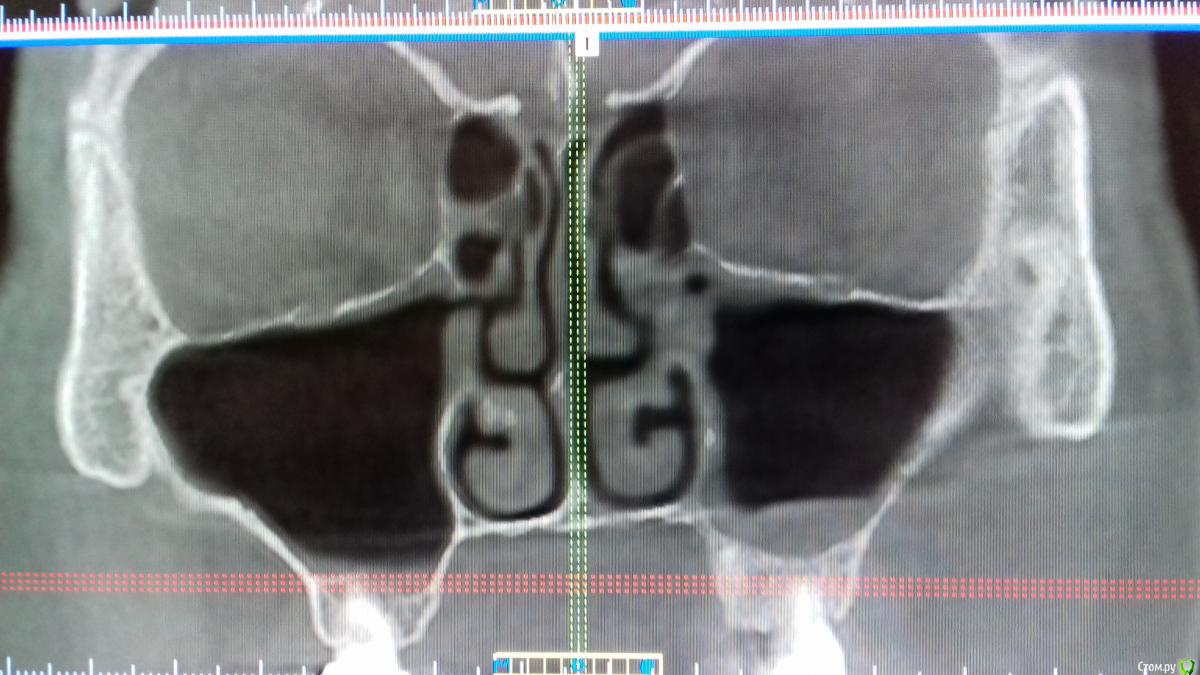

Хью Крейн Опубликовано 4 июня, 2018 Поделиться Опубликовано 4 июня, 2018 Уважаемые коллеги,нужен совет. Изначально план операции был таков:удаление корня 2.2,резекция верхушки корня 2.1, открытый синуслифтинг в области отсутствующего 2.5,вертикальная аугментация в области 2.3,2.4,2.5,консервация лунки 2.2. Закрытый остиум ставит в тупик. Пациент-курильщик. Недавно перенесено респираторное заболевание. 3.3 удален около 3 мес. назад по поводу локального парадонтального очага. Симптомов синусита не наблюдалось. К ЛОРу бы направить,но грамотного нет на примете. Ссылка на комментарий

Irouil Опубликовано 4 июня, 2018 Поделиться Опубликовано 4 июня, 2018 (изменено) Пробовать переделать КТ на фоне 2 недель гормона и гипертона в нос имхо Изменено 4 июня, 2018 пользователем Irouil Ссылка на комментарий